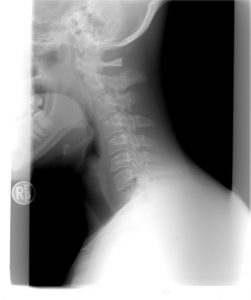

Rewolucyjna metoda łagodzenia bólu w odcinku szyjnym kręgosłupa: Niezwykłe ćwiczenia opracowane przez niemieckich specjalistów!

Czy jesteś jednym z tych, którzy zmagają się z uporczywym bólem szyi? Czy codzienne czynności stają się dla ciebie wyzwaniem? Oto przepis na ulgę! Poznaj technikę opracowaną przez specjalistów w dziedzinie bólu, Roland Libscher Brachta i dr Perta Brachta, której zadaniem jest skuteczna redukcja napięcia i bólu w odcinku szyjnym kręgosłupa.

Technika Libscher & Bracht – rezultat 30 lat intensywnych badań nad eliminacją bólu za pomocą terapii ruchowej i zmiany diety – to unikalny sposób na złagodzenie bólu szyi i karku. Ale co sprawia, że jest tak wyjątkowa? Szybkie odczucie ulgi i redukcji napięcia!